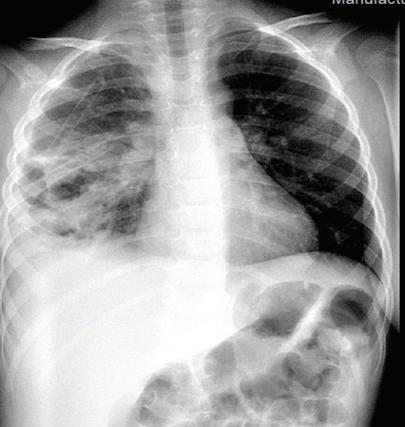

Придобитата в обществото пнев мония (ППО) все още остава чес та причина за заболяемост и смърт ност в световен мащаб. Честотата е най-висока при деца на възраст под 5 години и е от 10 до 40 случая на 1000 деца годишно[1,2]. Изчислено е, че ППО е причина за една пета от смъртните случаи при малки деца, с около два милиона смъртни случая годишно в развиващите се страни и развитият свят.

ност [СПИН] и тежка съпътстваща бе лодробна болест, като бронхиекта зии, кистична фиброза и хронична обструктивна белодробна болест [ХОББ])[8]. Известно е (главно на база та на проучвания на пунктати от бе лите дробове, проведени в развива щите се страни), че леката и умерена ППО се причинява главно от вируси, особено през първите години от жи вота, докато повечето случаи на теж ка ППО се причиняват от бактерии. Въпреки това е доказано, че грипни те вируси и респираторно-синцити алният вирус играят

в общността, където се на рича придобит в общността MRSA. Същият може да доведе до тежки бе лодробни инфекции, включително некротизираща и хеморагична пнев мония[7] Инфекцията с Pseudomonas aeruginosa е рядка при липса на спе цифични рискови фактори (скорош но антибиотично лечение, синдром на придобита имунна недостатъч

основна роля в причиняването на тежка и/или ус ложнена ППО. Значителен брой деца с ППО, причинени от атипични бак терии, показват сложно протичане, поради наличието на плеврален из лив[5] РИСКОВИ ФАКТОРИ И ЗАЩИТНИ МЕХАНИЗМИ НА ОРГАНИЗМА Микроорганизмите са разви ли разнообразни механизми, кои то благоприятстват колонизация та им в гостоприемника. Например, Парапневмонични усложнения – случаи от практиката Ю. Димитрова, Д. Хасанова, И. Цочева Отделение по педи атрия, УМБАЛСМ “Н. И. Пирогов” - София Придобитата в обществото пневмония все още остава честа причина за заболяемост и смърт ност в световен мащаб. Честотата е най-висока при деца под 5 години. S. pneumoniae и H. influenzae са водещите причинители на бактериална пневмония. При деца над 5-годиш на възраст зачестяват атипичните бактериални причинители - Mycoplasma pneumoniae и Chlamydophila pneumoniaе. Най-често тежките пневмонии, които протичат с усложнения, са вследствие на бактериални причинители и се изявяват с парапневмоничен излив, емпиема, мултилобарно заболяване, кавитарен абсцес, некротизираща пневмония, пневмоторакс, и бронхоплеврална фистула. ПЕДИАТРИЯ Ключови думи: Деца, ППО, парапневмонични усложнения.